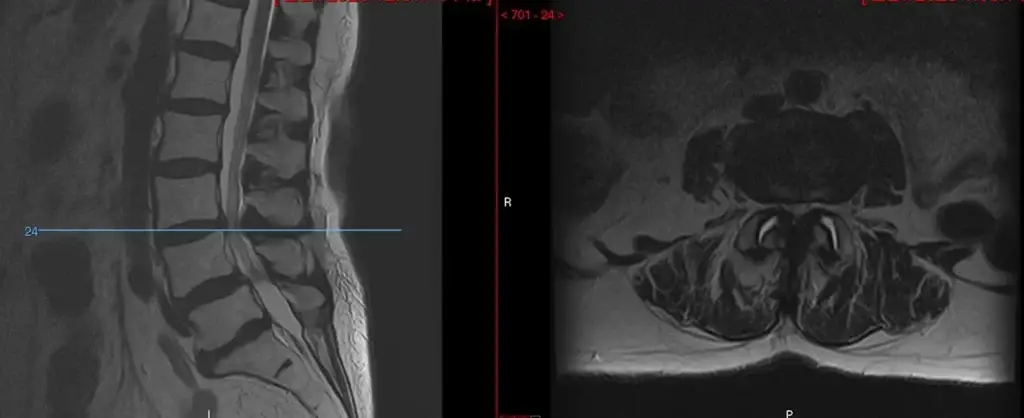

Unilateral Laminotomy and Bilateral Decompression (ULBD)